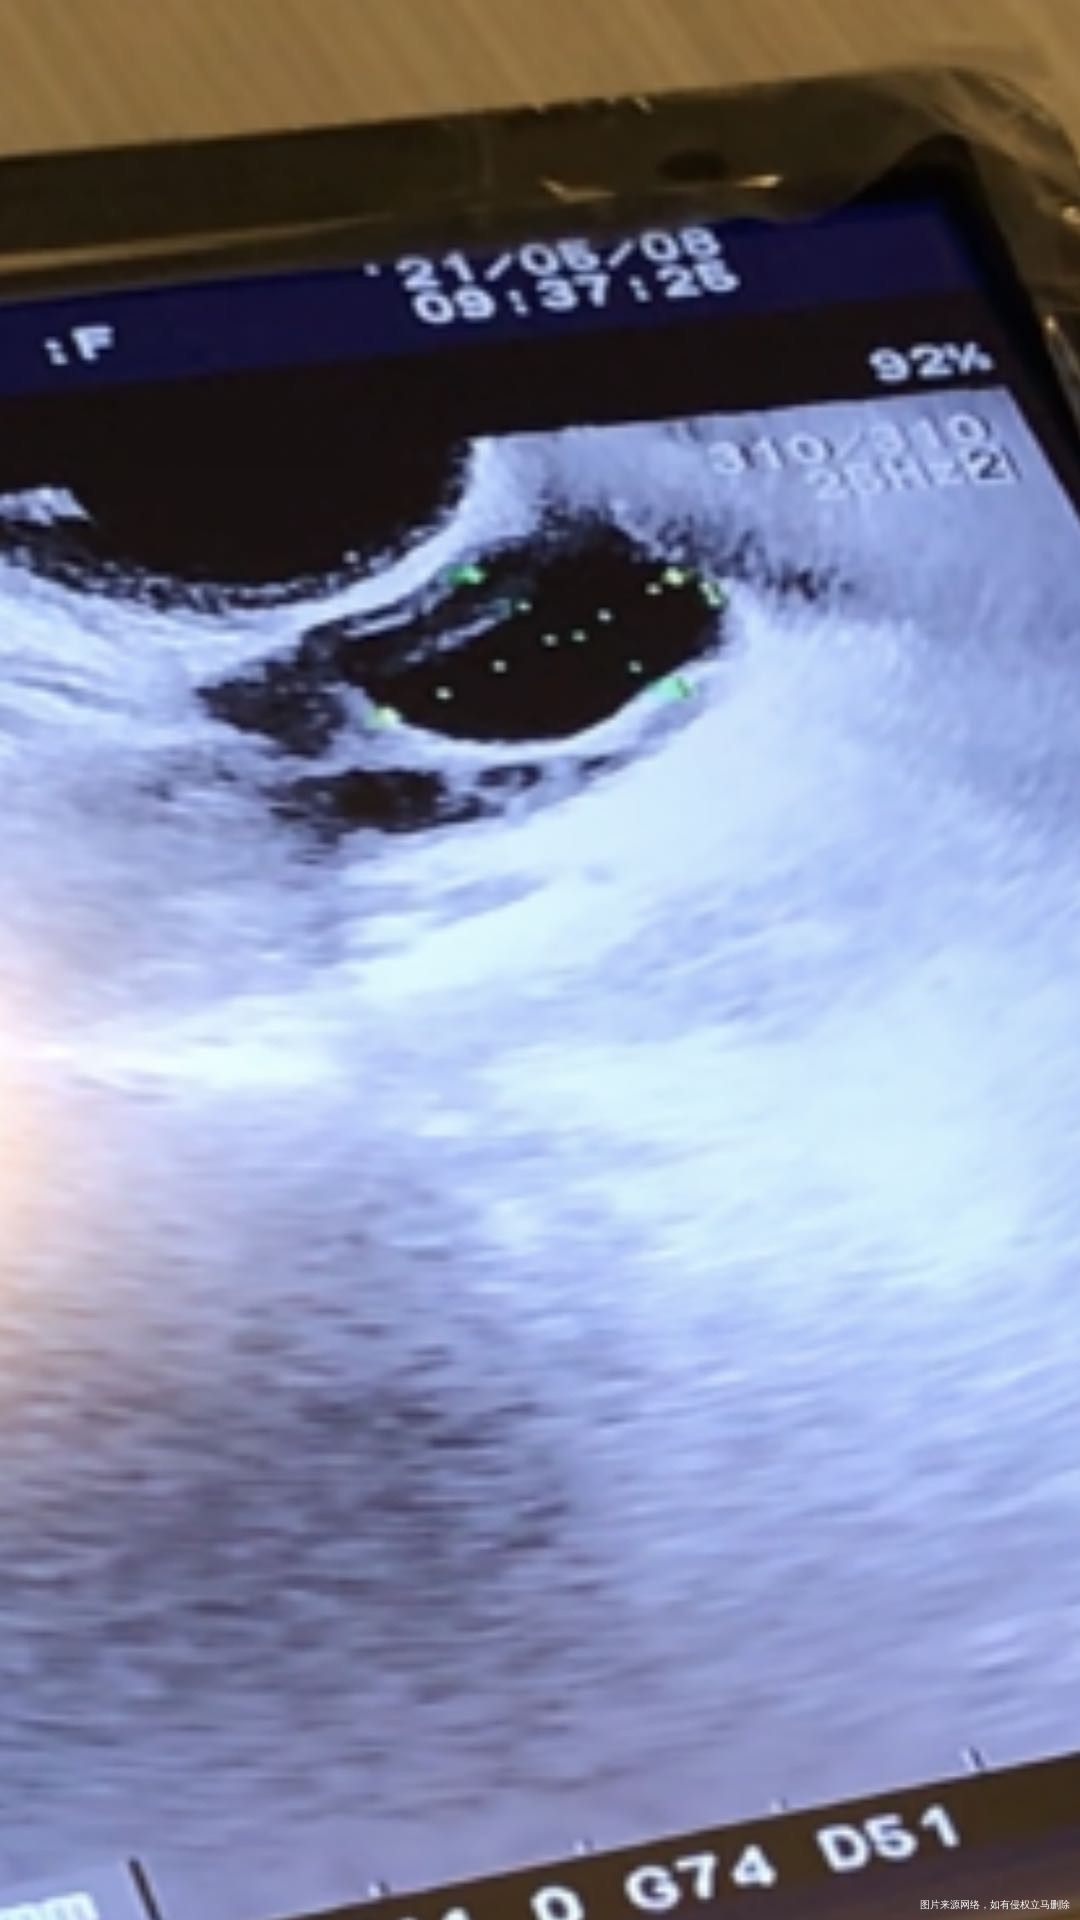

请医生帮忙看下b超图,卵泡20.7乘以14.5,内膜9.1,排卵试纸阴性,这个卵泡看起来张力不够是吗?这是感觉正在排卵还是马上要排了?还是卵泡长的不行?现在打破卵针是否合适?